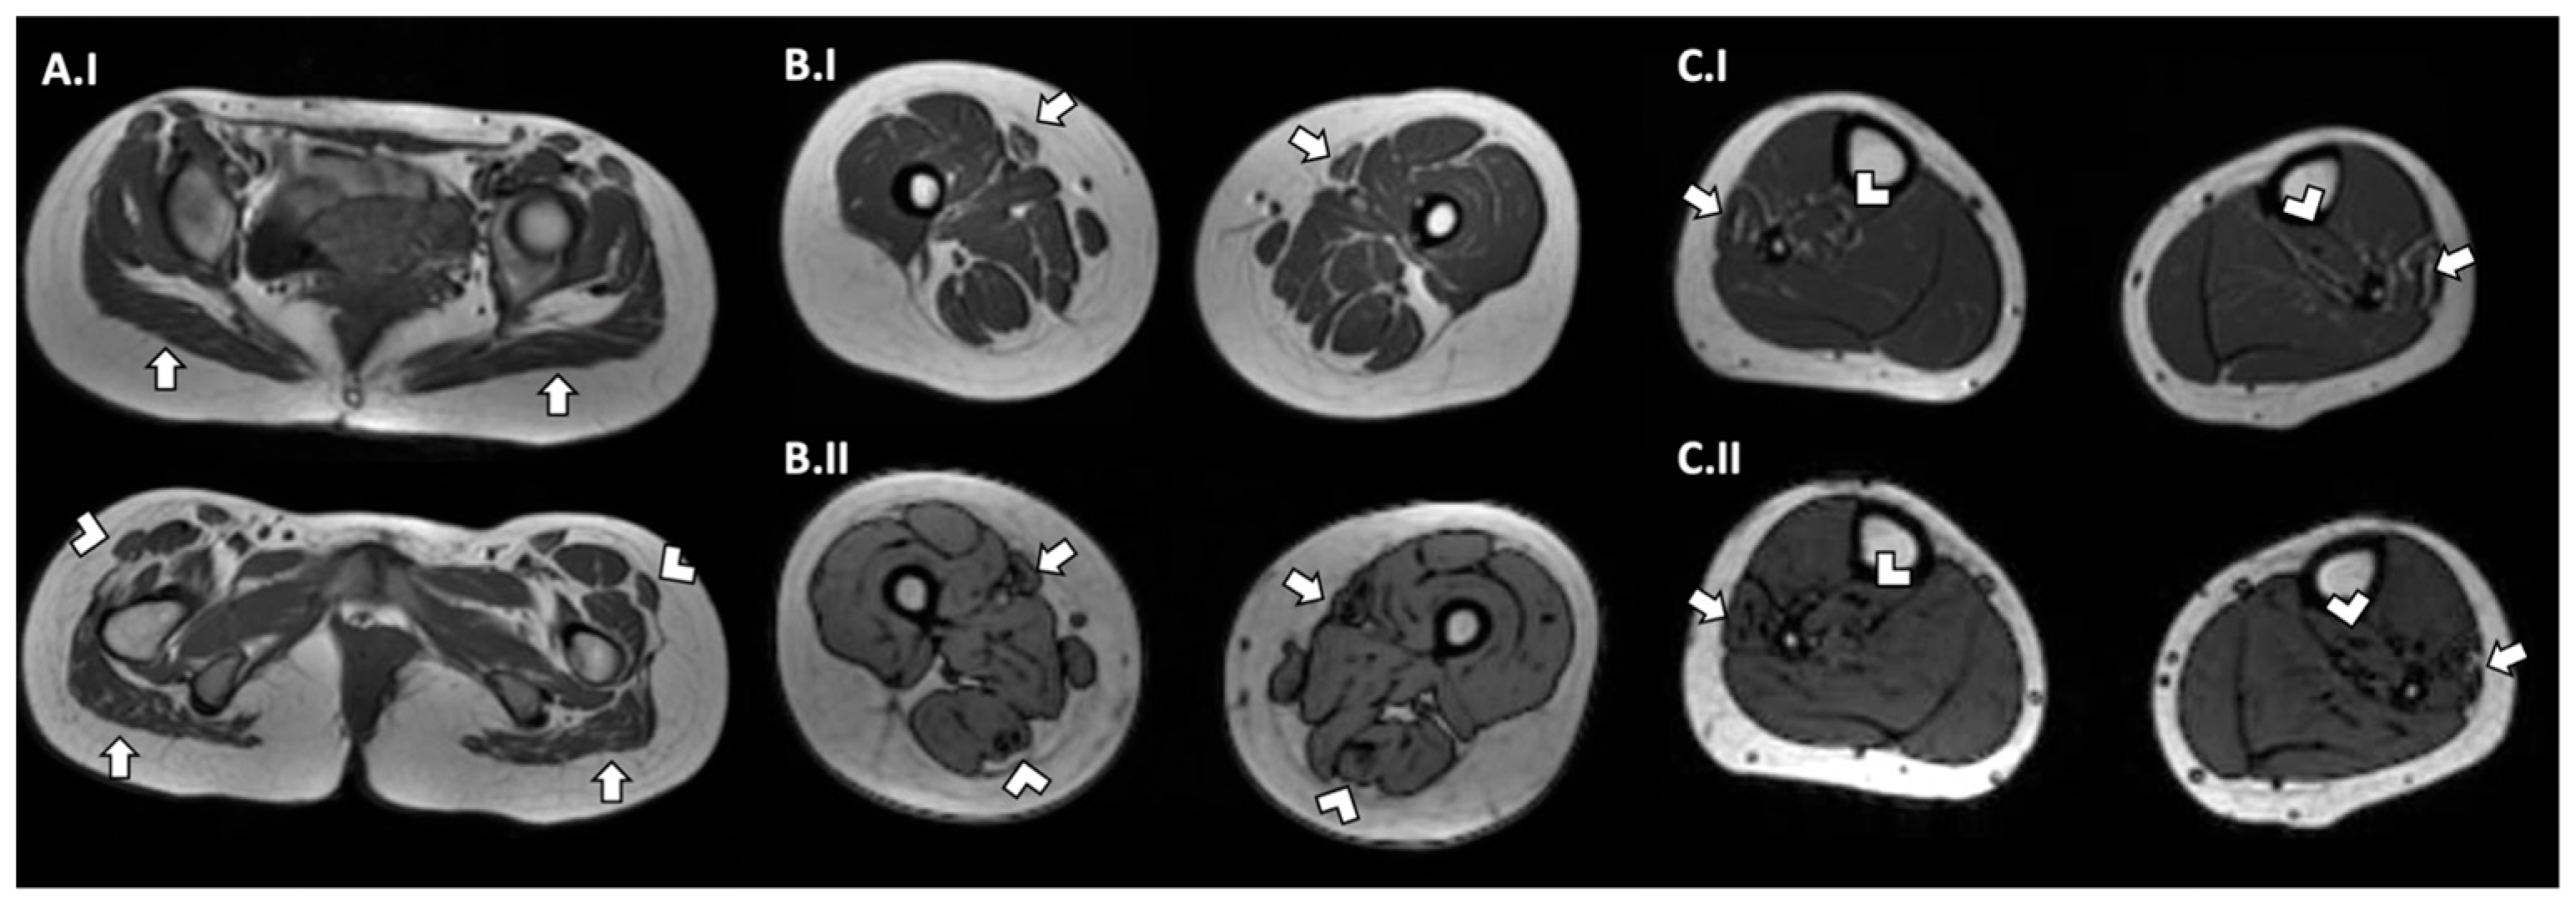

| Our case | 1 F | c.1394-2A>G; c.1724T>C, p.L575P | Neonatal | Delayed | Generalized (A and P > D) | Moderate | No | Slight swallowing problem | Mild | Yes | Reduced | No | No | Normal | Hypotrophy of pelvis and thigh muscles (> medio-posterior). Adipose infiltration of gluteus, tensor fasciae latae semitendinosus, sartorius, peroneus, and postero tibialis muscles | Fiber size variability, occasional internal nuclei, and disorganization of intermyofibrillar network |

| 3 M | c.4453C>T, p.Gln1485*; c.4967del, p.Leu1656Arg | Antenatal/ neonatal | Delayed | Proximal and axial | Mild with high arched palate | Yes | Slight swallowing problem | Mild | No | NA | NA | No | Normal | Fatty replacement and anterior muscle involvement in lower limb | Centralized nuclei; minicore; alveolar aspect of the inter-myofibrillar network; and uniformity of type I fibers | |

| 6 M | c.298G>T, p.Glu100Lys; c.3795G>T, p.Gln1265Hisfs*57 | Neonatal | Delayed | Generalized (A and P > D) | Mild with high arched palate and ptosis | Yes | Occasional swallowing difficulties | Severe | Yes | NA | NA | No | Normal | Marked atrophy involving all muscle groups of the upper leg bilaterally. Fatty infiltration, particularly of the extensor groups. | Fiber size variability; endomysial connective tissue around most fibers. Predominance of type I fibers | |

| 8 M | c.2225C>A, p.Pro742Gln | Early childhood | Delayed | Generalized | Mild with high arched palate | No | Normal | Mild | yes | NA | NA | No | Normal | Muscle wasting of the anterior thigh and no fatty infiltration | Fiber size variability and alveolar aspect of the intermyofibrillar network | |

| 9 M | c.2225C>A, p.Pro742Gln | Early childhood | Normal | Generalized | Mild with high arched palate | No | Normal | Mild | No | NA | NA | No | Normal | Muscle wasting of the anterior thigh and no fatty infiltration | Fiber size variability and alveolar aspect of the intermyofibrillar network | |

| 10 M | c.2224C>T, p.Pro742Ser | Antenatal/neonatal | Delayed | Generalized | Mild with high arched palate | Yes | Occasional swallowing difficulties | Severe | Yes | NA | NA | No | Normal | Diffuse atrophy and more severe fatty infiltration in anterior compartment of the thigh and soleus and peroneal muscles in the leg | Rare internalized nuclei; fiber size variability; alveolar aspect of the inter-myofibrillar network; and uniformity of type I fibers | |

| 11 M | c.4099C>G, p.Leu1367Val | Early onset (6–7 months) | Delayed | Generalized (more severe at upper member and P > D at lower members) | Mild with high arched palate | No | Occasional swallowing difficulties | Mild | Yes | NA | NA | No | Elevated (1000–2000) | Severe changes in thigh (anterior > posterior) and relative sparing of anterior compartment in the leg | Internalized nuclei; core-like structures; fiber size variability; and endomysial fibrosis | |

| 12 F | c.4099C>G, p.Leu1367Val | Neonatal | Delayed | Generalized (more severe at upper member and P > D at lower members) | Mild with high arched palate | No | Occasional swallowing difficulties | Mild | Yes | NA | NA | No | Elevated (1000–2000) | Severe changes in thigh (anterior > posterior) and relative sparing of anterior compartment in the leg | NA | |

| Morales et al. [19] | 16 F | c.2970G>A, p.Trp990*; c.5104C>T, p.Arg1702* | Neonatal | NA | Proximal and axial (mild) | NA | NA | Slight swallowing problem | Severe | NA | NA | NA | NA | Normal | Upper and lower limbs atrophy. No fat tissue replacement | Non-specific myopathic pattern with type 1 fiber predominance and mild myofibrillar disorganization |

| 17 M | c.2447T>G, p.(Leu816Arg) | Neonatal | NA | Proximal lower members | Mild with high arched palate | NA | Slight swallowing problem | Severe | NA | NA | NA | NA | Normal | Involvement of gluteus maximum | Non-specific myopathic pattern with type 1 fiber predominance | |

| Mauri et al. [22] | 20 F | c.3364 T>C, p.Tyr1122His | Adult | NA | Generalized (P > D) | Mild with ptosis | NA | Slight swallowing problem | Moderate | NA | NA | NA | No | Normal | Diffuse hypotrophy, more prominent in the right deltoid muscle | Rare nuclear clumps, fiber size variability and few type II angulated and grouped hypotrophic fibers; and focal zones of myofibrillar disorganization |